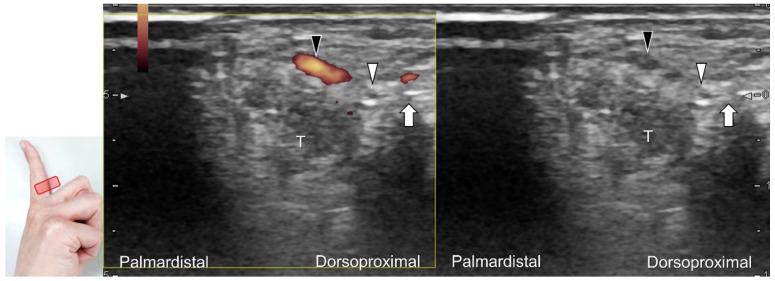

超声已成为一种极具价值的工具,用于腕部区域周围神经病变的成像,特别是对于诸如腕管综合征和尺神经管综合征等常见病症。大量研究表明,神经在卡压部位近端肿胀、边界不清和平扁是神经卡压的特征。然而,关于腕部和手部的小神经或终末神经的信息却很匮乏。本文旨在通过全面概述这些神经卡压的扫描技术、病理学和引导注射方法来填补这一知识空白。本综述详细阐述了正中神经(主干、掌皮支和返支)、尺神经(主干、浅支、深支、掌尺皮支和背尺皮支)、桡浅神经、骨间后神经、掌总/指固有神经和背总/指固有神经。一系列超声图像用于详细说明这些技术。最后,超声检查结果补充了电诊断研究,有助于更好地理解整个临床情况,而超声引导下的干预措施对于治疗相关神经病变是安全有效的。